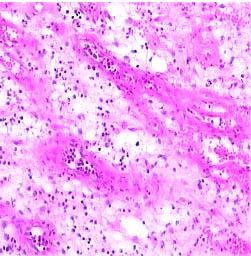

肉芽组织(granulation tissue)是指由新生薄壁的毛细血管以及增生的成纤维细胞构成,并伴有炎性细胞浸润,肉眼表现为鲜红色,颗粒状,柔软湿润,形似鲜嫩的肉芽故而得名。为幼稚阶段的纤维结缔组织。

1.肉眼观察 肉芽组织的表面呈细颗粒状,鲜红色,柔软湿润,触之易出血而无痛觉,形似嫩肉故名。

2.镜下观察 基本结构为:

①大量新生的毛细血管,平行排列,均与表面相垂直,并在近表面处互相吻合形成弓状突起,肉眼呈鲜红色细颗粒状。

②新增生的纤维母细胞散在分布于毛细血管网络之间,很少有胶原纤维形成。

③多少不等的炎性细胞浸润于肉芽组织之中。肉芽组织内常含一定量的水肿液,但不含神经纤维,故无疼痛 。